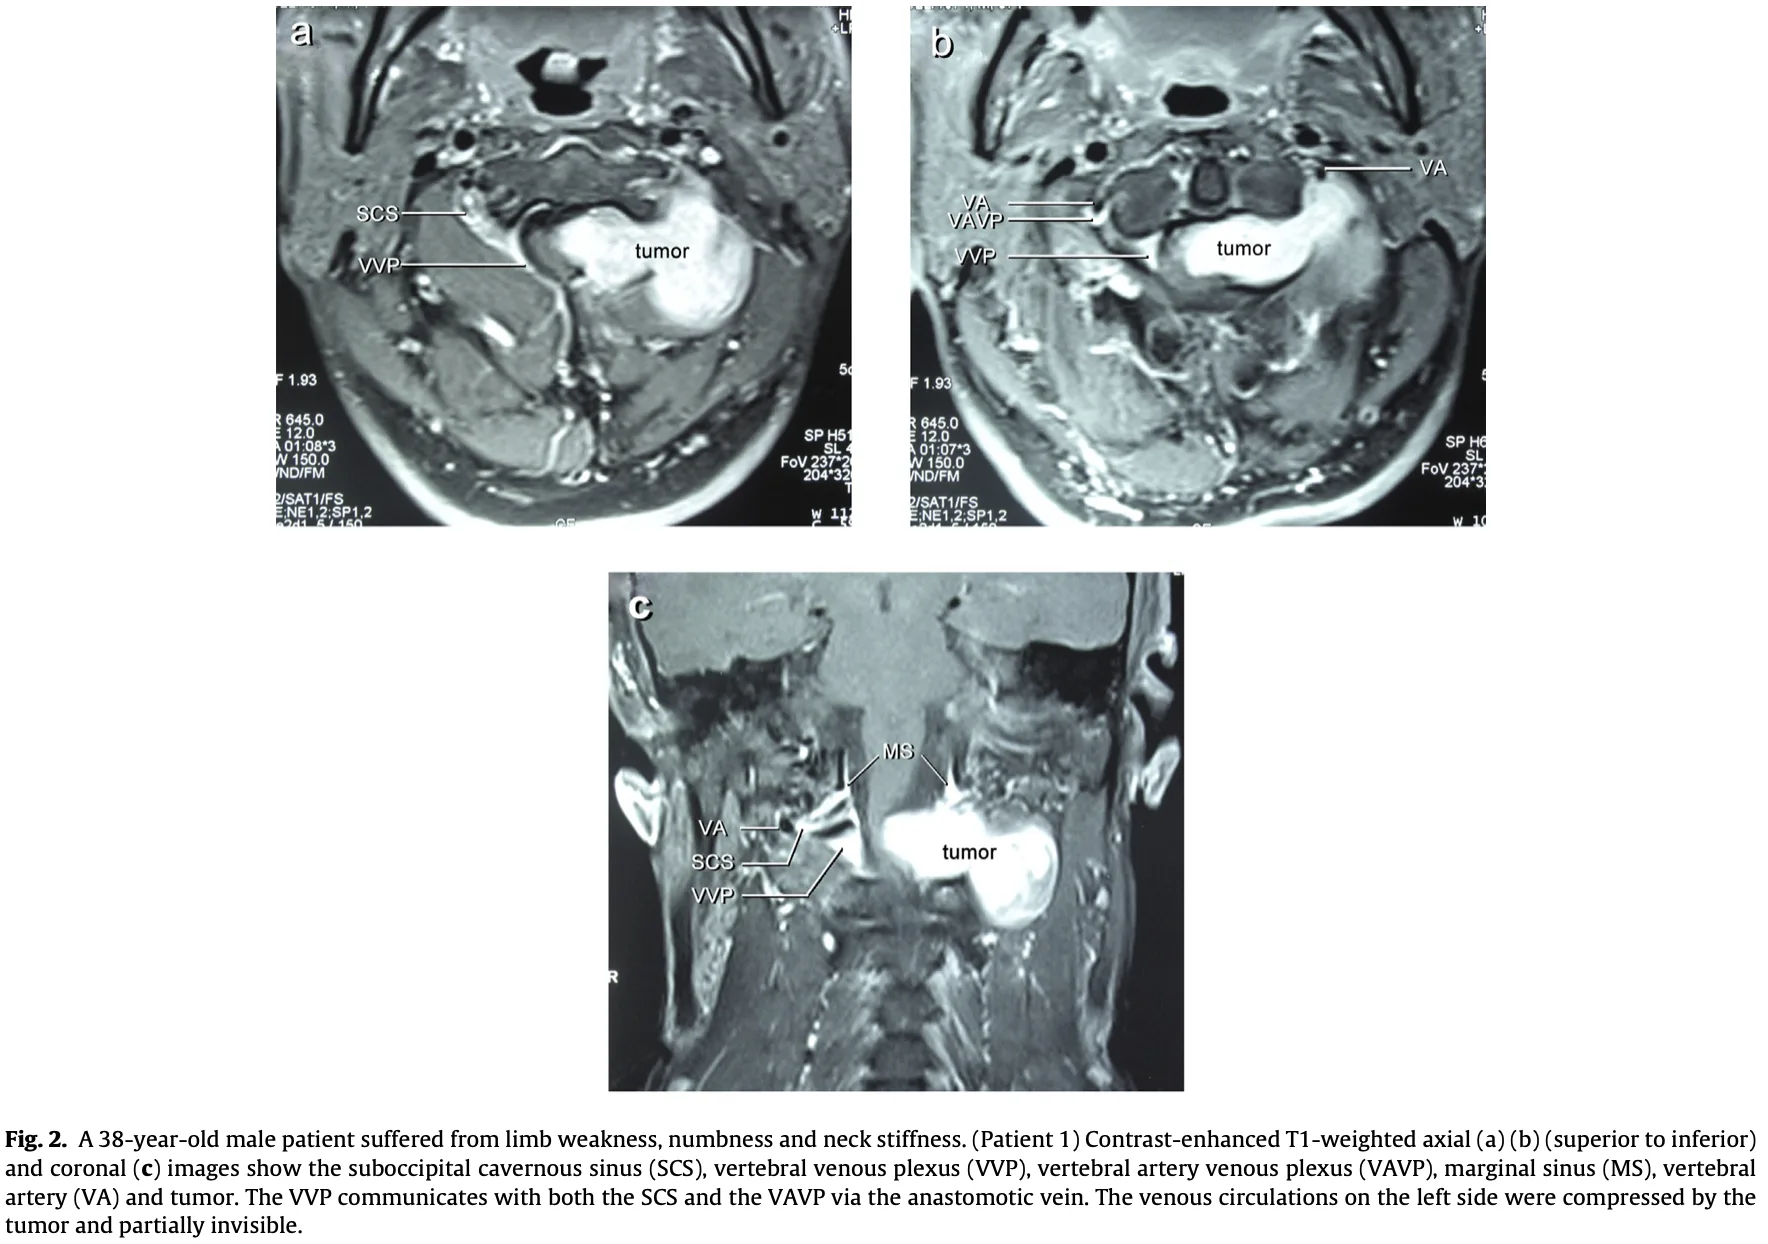

頚椎ダンベル腫瘍

形成外科から, 頚部腫瘍を指摘された中高年の患者さんが紹介され, 受診されました.

「MRIで, 頚髄とつながっているように見える」

との情報でした。

MRIでは, 第1/2頚椎椎間孔から頚部後方へ隆起する腫瘍性病変を認め, 第2頚神経根から発生した神経鞘腫 と診断しました.

脊柱管内から神経根に沿って椎間孔を通り, 外側(傍脊柱)へと砂時計状に広がる腫瘍は, その形状からダンベル腫瘍と呼ばれます.

多くは良性の神経鞘腫です.

脊髄や神経根が圧排されると, 感覚障害, しびれ, 筋力低下などの麻痺症状を呈しますが, この患者さんは幸い, 現時点では症状は認められませんでした.

大学病院の整形外科および脳神経外科での精査・治療を勧め, 予約を取りました.